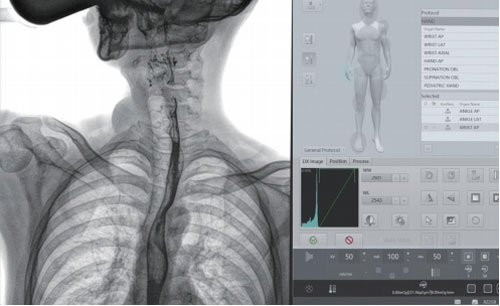

● Quickly select and preset the desired field of view, saving time in positioning;

● One key switching of the beam range , efficient and convenient.

● Intelligent remote sensing, making physician examinations easy and convenient.

● All the operating buttons are accompanied by text and icons, making it easy and convenient.

SID 1800mm electric stretching, meet the needs of chest radiography in radiology department.

The detector can be moved in large scale which eliminates the need for Patient re-positioning.